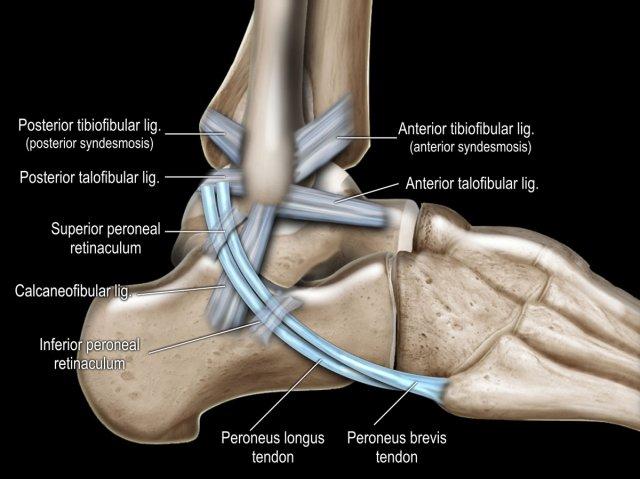

Có ba dây chằng ở phía ngoài:

- Dây chằng sên mác trước (anterior talofibular ligament – ATFL)

- Dây chằng gót mác (calcaneofibular ligament – CFL)

- Dây chằng sên mác sau (posterior talofibular ligament – PTFL).

Dây chằng ATFL chạy từ mắt cá ngoài ra phía trước đến bờ ngoài của xương sên.

Dây chằng này có hướng nằm ngang và được quan sát rõ nhất trên ảnh cắt ngang.

Đây là dây chằng bị tổn thương thường gặp nhất ở cổ chân và cũng là dây chằng đầu tiên bị tổn thương ở phía ngoài.

Điều này có nghĩa là khi dây chằng CFL hoặc PTFL bị tổn thương, rất có khả năng dây chằng ATFL cũng đã bị tổn thương.